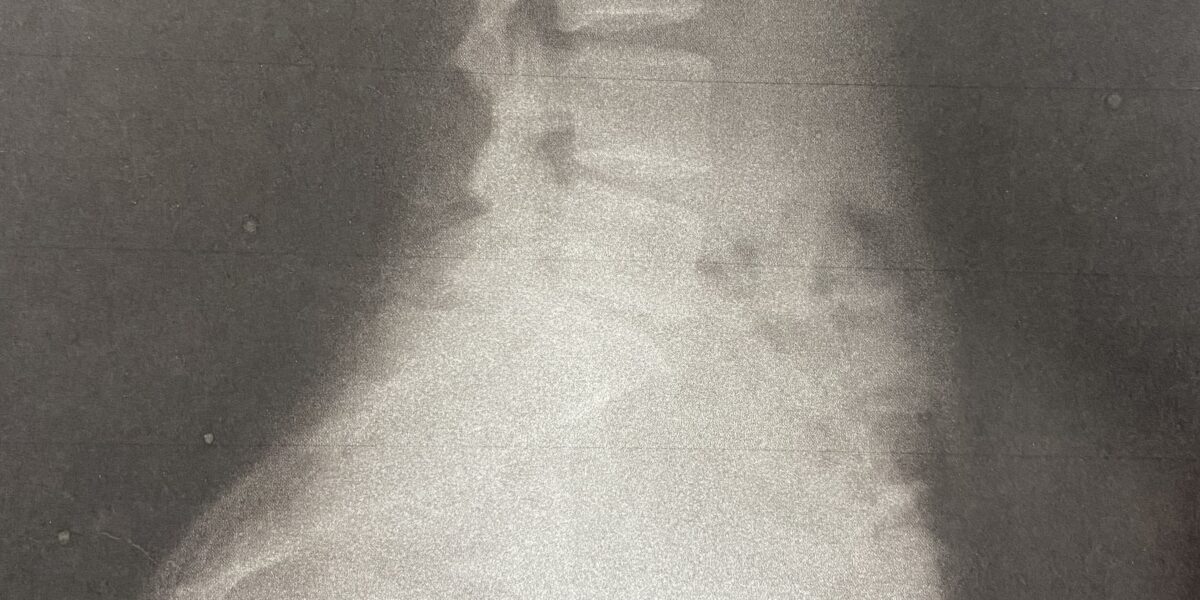

ヘルニアは診断してもらったわけではないのですが

なかなかすごい反り方しています(笑)

この写真を持っていることも、偶然ではなく自分の身体への興味で 負傷したわけでもないのにレントゲンを撮ることができ、しかもコピーにとって自分で持っています。